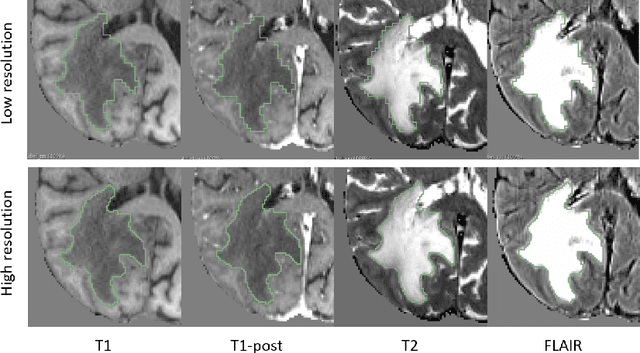

Abstract:Deep learning has quickly become the weapon of choice for brain lesion segmentation. However, few existing algorithms pre-configure any biological context of their chosen segmentation tissues, and instead rely on the neural network's optimizer to develop such associations de novo. We present a novel method for applying deep neural networks to the problem of glioma tissue segmentation that takes into account the structured nature of gliomas - edematous tissue surrounding mutually-exclusive regions of enhancing and non-enhancing tumor. We trained multiple deep neural networks with a 3D U-Net architecture in a tree structure to create segmentations for edema, non-enhancing tumor, and enhancing tumor regions. Specifically, training was configured such that the whole tumor region including edema was predicted first, and its output segmentation was fed as input into separate models to predict enhancing and non-enhancing tumor. Our method was trained and evaluated on the publicly available BraTS dataset, achieving Dice scores of 0.882, 0.732, and 0.730 for whole tumor, enhancing tumor and tumor core respectively.